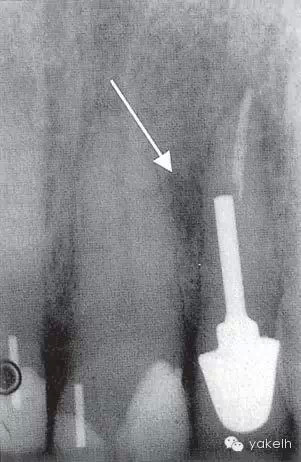

¤¤在征得患者同意后,最終選擇根管外科手術(shù)修復(fù)穿孔。局麻下翻開(kāi)三角形全厚黏骨膜瓣,充分暴露骨和根面;使用刮匙去除穿孔上覆蓋的肉芽組織,暴露穿孔和樁(圖5.4.2a);使用外科專(zhuān)用渦輪手機(jī)配以金剛砂小球鉆,去除樁的尖端;使用超聲銼去除根管末端的牙膠,并進(jìn)行根管預(yù)備(圖5.4.2b);預(yù)備后的根管與穿孔部位使用IRM嚴(yán)密封閉(圖5.4.2c);瓣復(fù)位、縫合固定,拍攝術(shù)后X線片(圖5.4.3a);3天后拆線。

圖5.4.3(a)22術(shù)后X線片,顯示穿孔修復(fù)、根管末端充填。